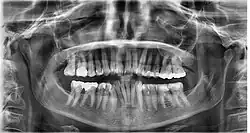

Dental

Dental radiograph

Dental examination is a method of body identification that involves the comparison of antemortem and postmortem dental records, such as radiographs and photographs.[18] The jaw is analysed to detect any peculiarities in the teeth or any diseases.[18] In the scenario where skin prints are unable to assist in the process of identification, dental examination can be used.[19] The Forensic Dentistry and Anthropology Center of the Dental Faculty of Piracicaba analysed radiographs and dental records of a "surgically implanted orthopedic plate"[19] to successfully identify a burned body. The success of dental identification can be tainted if the individual has endured a physically traumatic experience that has caused damage to their teeth and jaw.[20] In this scenario, DNA identification is used in the process of body identification.